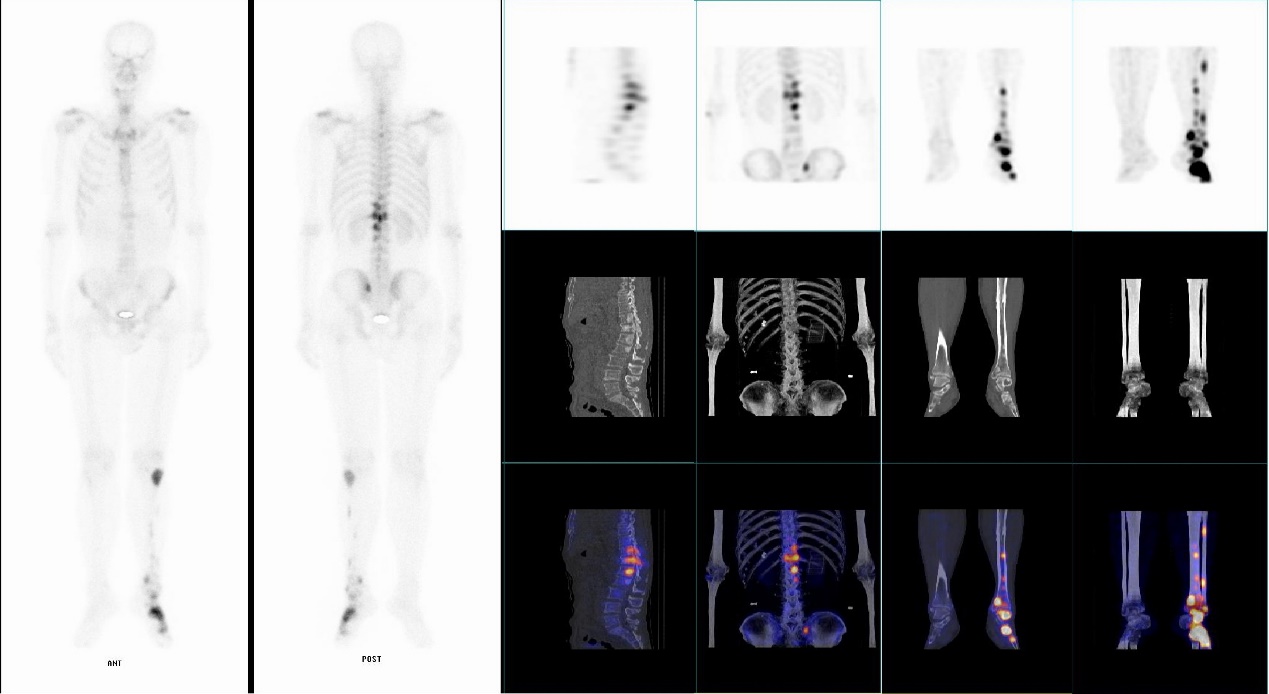

1.核医学显像和功能诊断

目前核医学常规运用的大型检查仪器有:SPECT/CT、PET/CT等,属于多功能分子影像设备,还有甲状腺功能测定仪、双能X线骨密度仪等传统检查设备;可用于了解内分泌、心血脏、神经系统、泌尿系统、呼吸系统及骨骼系统等多方面疾病情况,特别是在肿瘤病人选择治疗方案上发挥重要作用。

核医学诊断主要工作原理为通过静脉注射或者口服等方式将放射性药物(显像剂等)引入到体内之后,利用核医学SPECT/CT、PET/CT检查仪器,探测放射性药物在体内分布情况,从而显示出病变的位置、数量及代谢等信息,从而为临床诊断、治疗方案选择、疗效判断等提供依据。

苏州九院核医学科现有GE OPTIMA640型SPECT/CT仪一台,可以常规开展单光子核素显像,如肾脏动态显像、骨显像、脑血流灌注显像、心肌血流灌注显像、唾液腺显像、甲状腺显像、甲状旁腺显像、肾上腺髓质显像、淋巴显像、消化道出血显像、肝胆动态显像、异位胃黏膜显像等检查,为临床疾病诊断和治疗提供帮助。有JXY-Ⅱ型甲状腺摄碘功能测量仪一台,用于检测甲状腺组织对碘的摄取能力和碘在甲状腺组织中的有效半衰期,为甲状腺疾病诊疗提供依据。